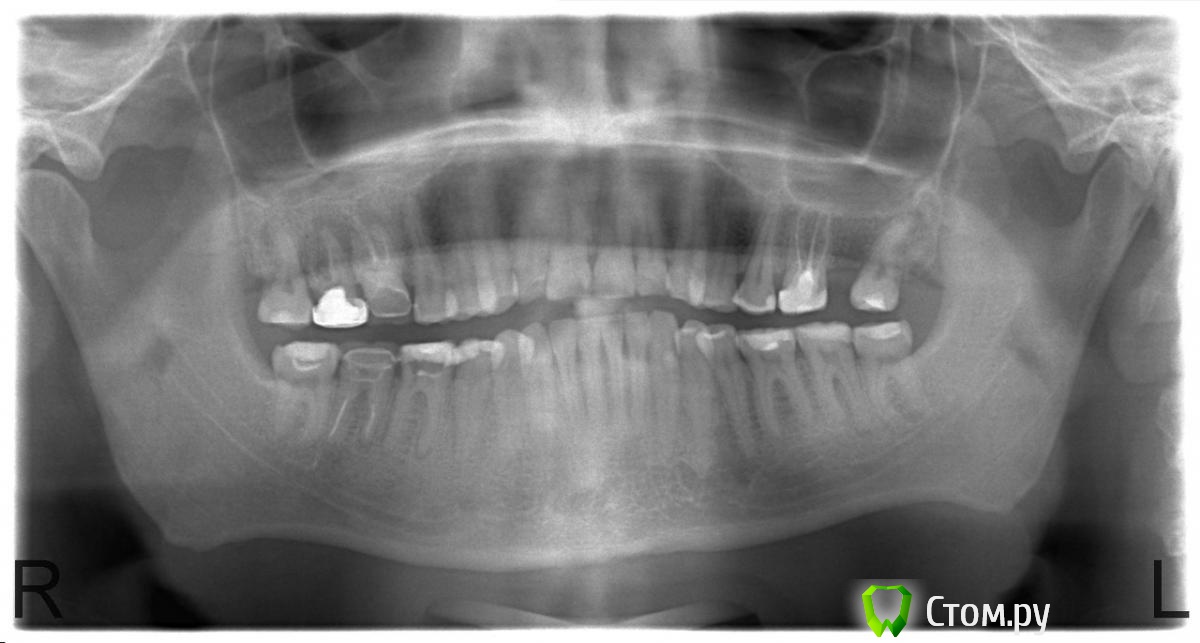

axtrace Опубликовано 13 июля, 2014 Автор Поделиться Опубликовано 13 июля, 2014 Прикрепляю панорамный снимок: https://yadi.sk/i/yk5MbfiMWX88hДобрый день! Предыстория: Поставили пломбу на 46 (он был разрушен более чем на 1/2). Три месяца походил, начал реагировать на холодное, через два-три дня - пока дошел до врача - отдавать в кость. Когда начал отдавать в кость, стал сомневаться, 46 ли это - реально стало не понятно. Врач попробивала зубы током, оказалось, что самое большой ток в 48 - поставила туда мумифицирующее и еще что-то.Боль не прошла.Вернулся через три дня - мумифицирующее и еще что-то поставили в 46, стало гораздо легче.Особенность НИИ такова, что в очередях надо ждать по 3 часа. При том, что там есть запись.Когда я вернулся на пломбировку каналов, прождал опять несколько часов и сбежал оттуда (это было в минувшую среду).Сегодня был на приеме у терапевта в другой клинике - сделали панорамный снимок, вскрыли временные пломбы, попытались разобраться, что делали в предыдущем месте, увидели проблему в 46 - у основания канала очажок воспаления. Поставили временную пломбу, отпустили с миром.Предложили план лечения:46 - пломбировка каналов, коронка.48 - пока пломбу, сколько проходишь, столько и проходишь. Потом удаление зуба. Так как врач будет в отпуске, все это назначено на через 10 дней. Но зуб ноет, особенно по ночам. Подскажите, насколько такой план выглядит адекватным и не надо ли принимать срочных мер?10 дней ходить на обесболивающих? Ссылка на комментарий

art700 Опубликовано 13 июля, 2014 Поделиться Опубликовано 13 июля, 2014 Лечить 47, 46, это то что я смог увидеть, ибо с айпада ваш снимок открывает плохо, суда выложите лучше 1 Ссылка на комментарий

red_butler Опубликовано 13 июля, 2014 Поделиться Опубликовано 13 июля, 2014 (изменено) Требуется полноценная механическая и медикаментозная обработка и пломбирование корневых каналов, это делается за одно посещение. У вас в профиле не указан город, Но надеюсь клиник больше двух, найдите стоматолога-терапевта который вылечит зуб, если болит ждать еще 10 дней не стоит. Затем протезирование. Что касается зуба мудрости, я бы его удалил, если оставлять - То так же лечить корневые каналы и протезировать. Да, 3.7 тоже лечить Изменено 13 июля, 2014 пользователем red_butler 1 Ссылка на комментарий

DokDent Опубликовано 13 июля, 2014 Поделиться Опубликовано 13 июля, 2014 10 дней ждать и пить обезболивающие-не вариант. 46 пломбировать каналы и коронка, в 48 если клали мумифицирующее в-во (с Ваших слов) если это так, значит просто пломбой не обойдёшься, и тоже надо пломбировать каналы (хотя по этому снимку вскрытого рога пульпы я не вижу), возможно Вы ошиблись. В 47 тоже есть изменения на корнях. И сверху зубы-антагонисты могут беспокоить. 1 Ссылка на комментарий